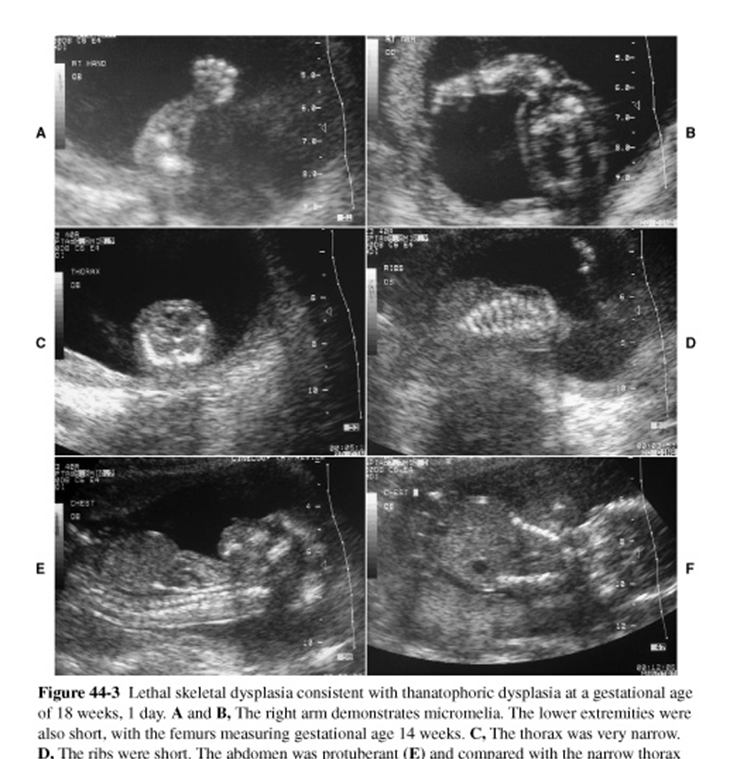

What are these images showing?

Thanatophoric Dysplasia